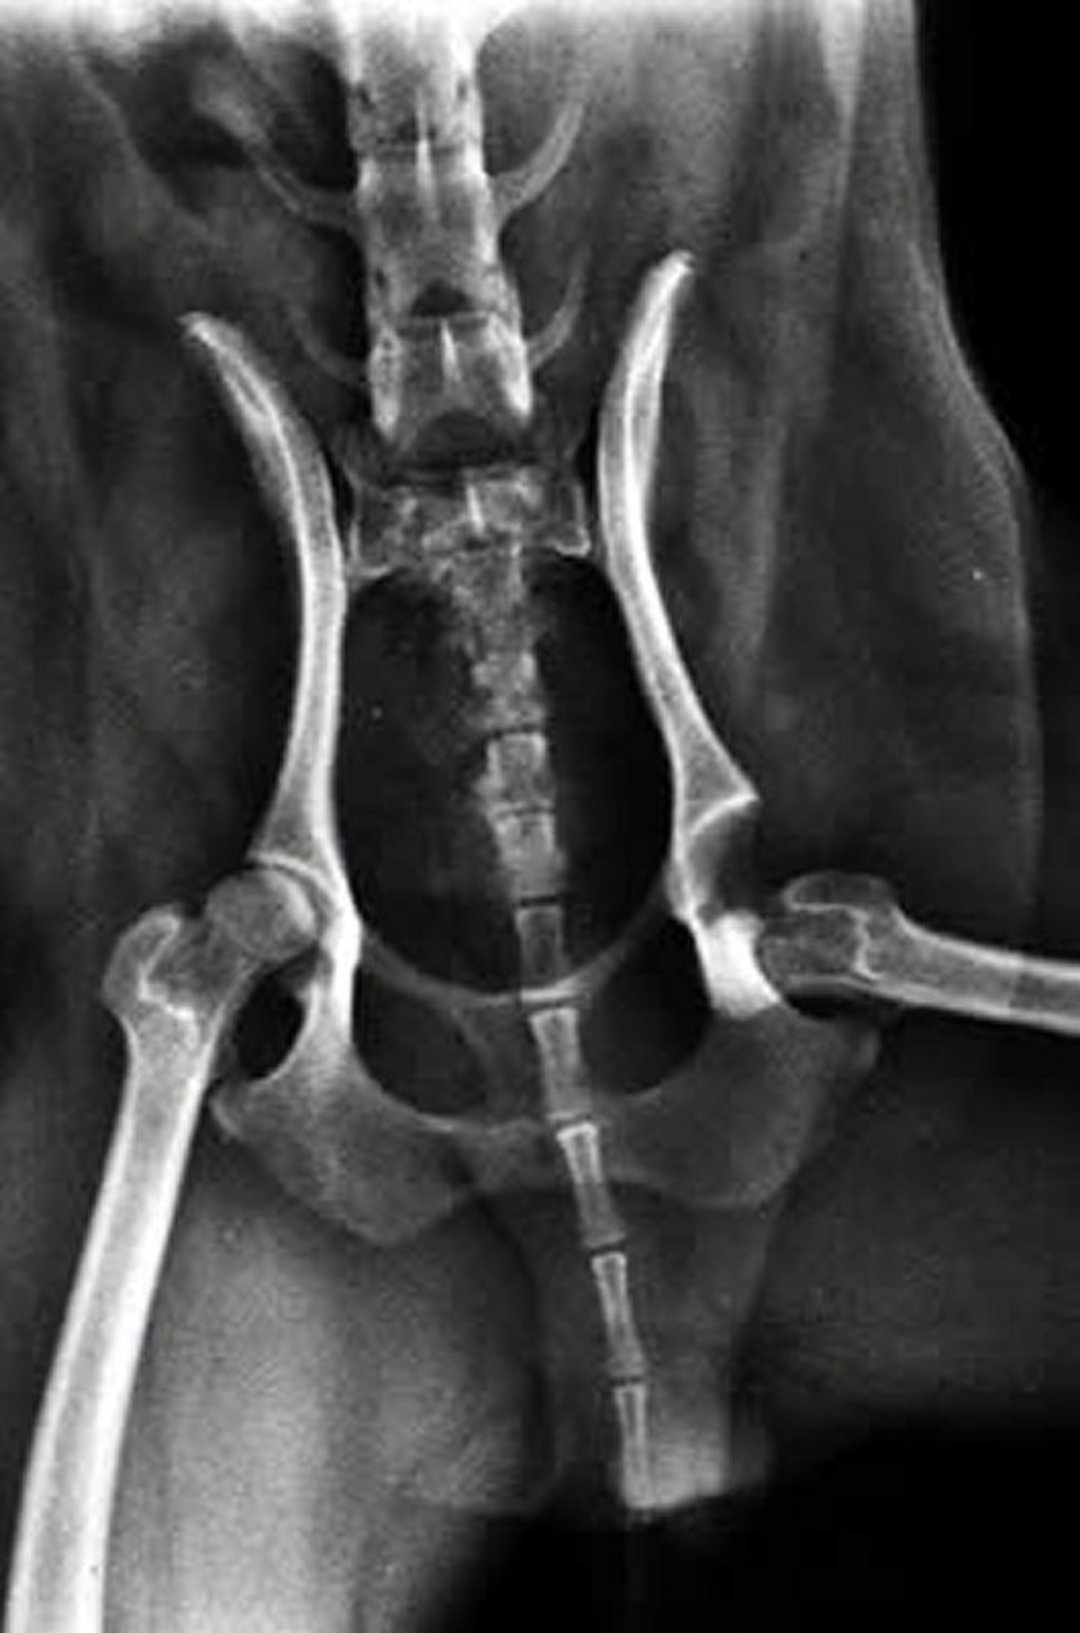

Ventrodorsal radiographic view of a dog with hip luxation. Note the caudal luxation of the left femoral head relative to the acetabulum.